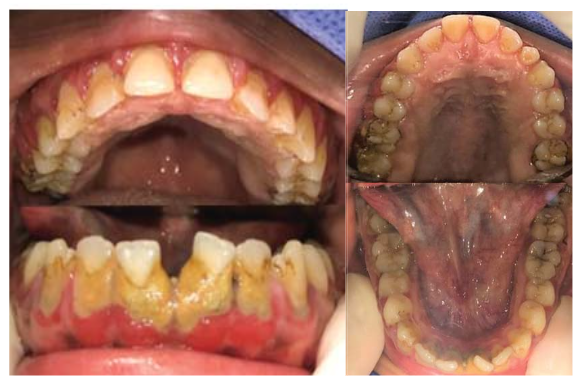

El examen intraoral es limitado por la poca colaboración del paciente, permitiendo observar únicamente la zona anterior de ambos maxilares, en los que se evidencia acúmulos de placa dura y blanda, encías eritematosas y lesiones cariosas. Se presume presencia de lesiones cariosas en sectores posteriores, acúmulo de placa generalizada, presencia de terceros molares; como diagnósticos por confirmar.

Bajo los efectos de la AG y entubado por vía nasal, se procede a realizar la evaluación clínica, la toma de radiografías periapicales necesarias (figura 2), set fotográfico de control (figura 3), la confirmación de los diagnósticos y reconfirmación del plan de tratamiento. El plan de tratamiento incluyó: la eliminación del tártaro dental y pulido de las piezas dentarias, obturaciones de resinas y la eliminación de las terceras molares de los cuatro cuadrantes. Se consideró la permanencia de la pieza supernumeraria ubicada entre las piezas 2.2 y 2.3, por encontrarse en el arco dental sin alterar la oclusión. Se instala el tapón faríngeo, continuando así con el inicio el tiempo operatorio de 2 horas y 30 minutos. Durante la AG el paciente no presento alteraciones en su frecuencia cardiaca ni respiratoria u algún reporte de interés por parte del personal de anestesiología.

Para este momento se evidencia el cambio evidente en el periodonto, la coloración de la gingiva se presenta rosa, sin apariencia edematosa ni sangrado al contacto y un adecuado proceso de cicatrización de las zonas retromolares, además de aumento en su apetito y estado de ánimo en casa referido por los padres.